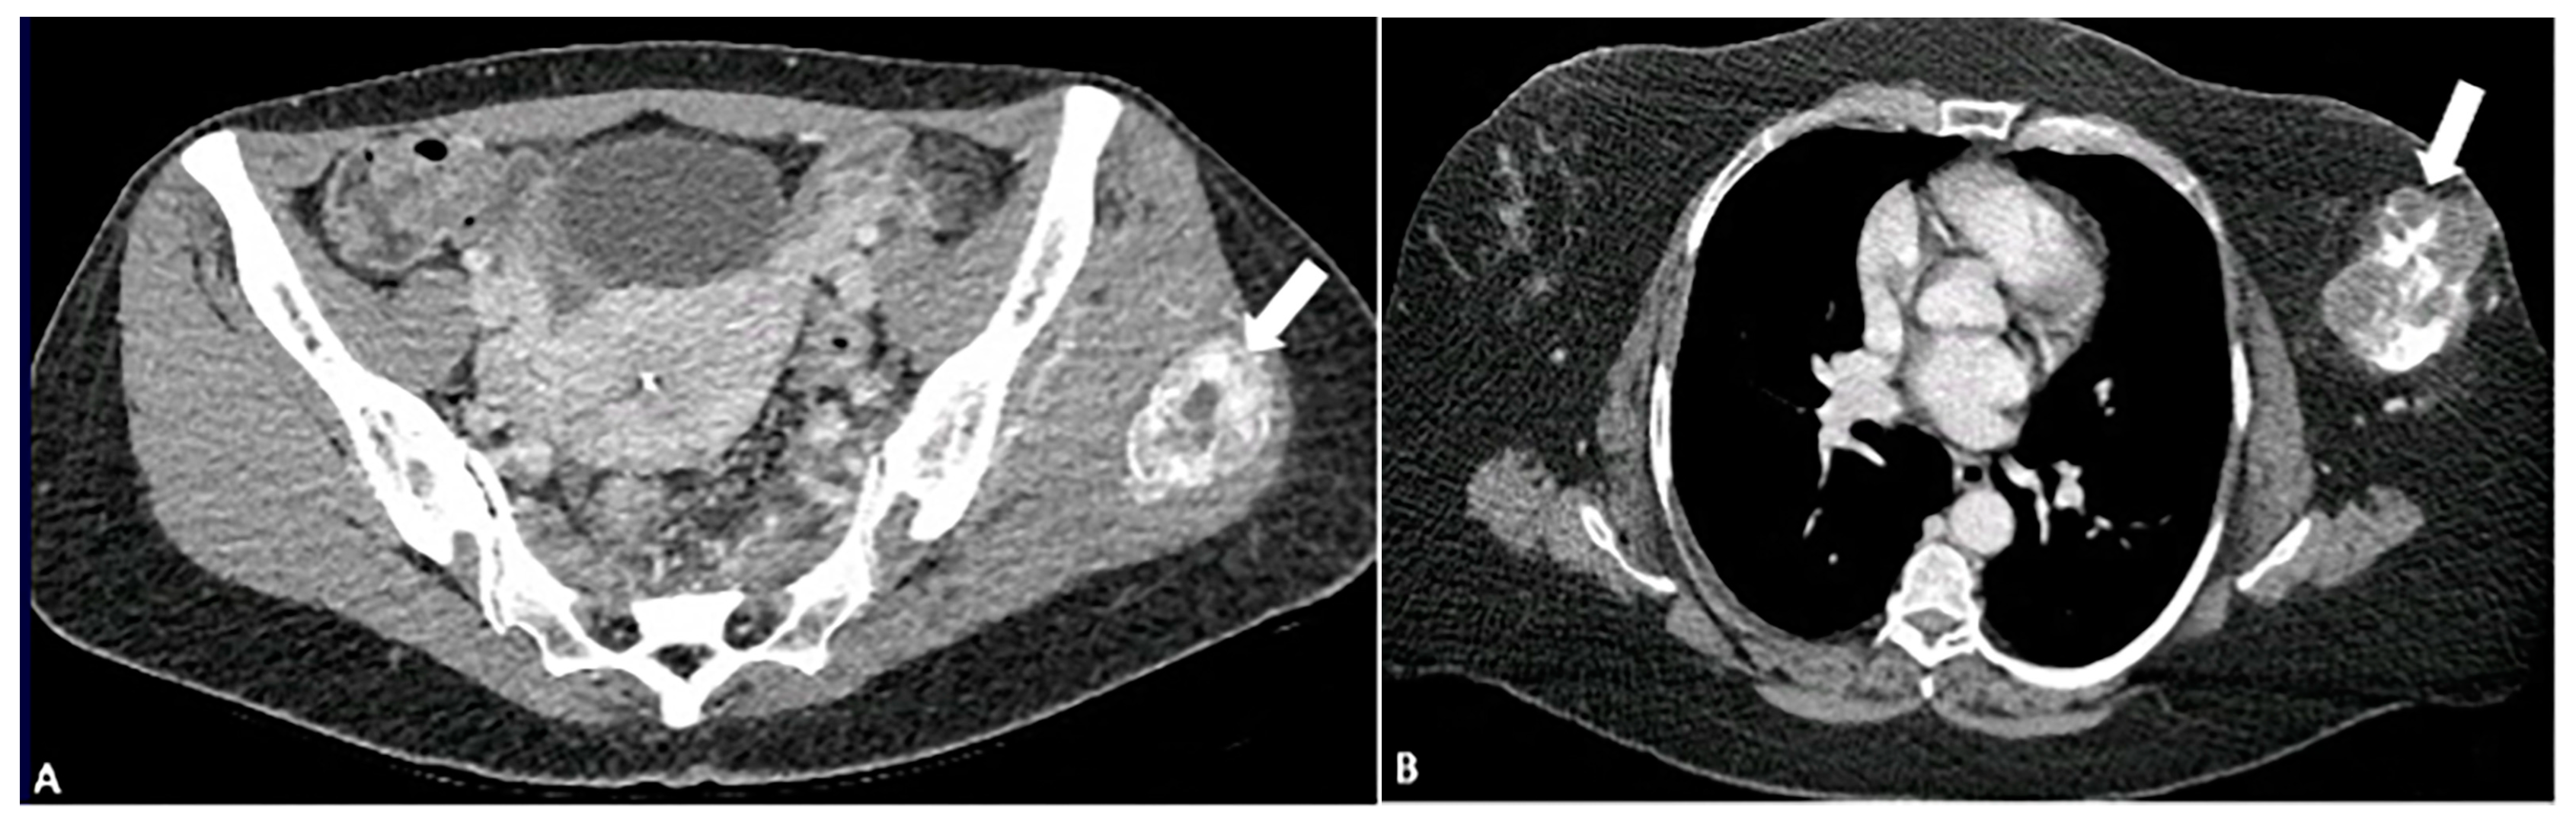

5.2.1. Gout

5.2.2. Primary Tumoral Calcinosis